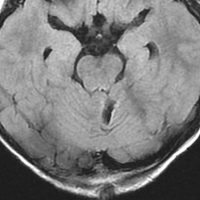

手術翌日のMRIです。小脳失調症状の出現はなく,抜糸してすぐに退院して普通の生活に戻れました。

この画像を見れば,後頭下開頭テント下法 infratentorial approach では,小脳切断しなければ腫瘍に届かないことが理解できると思います。